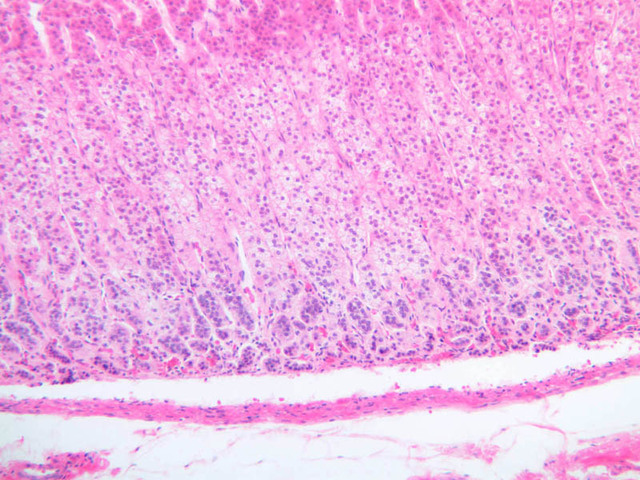

The zona glomerulosa is located immediately beneath the capsule (B-60 adrenal gland, dog [10x, 20x] [20x, 40x]; B-59 [2.5x, 10x, 20x] [2.5x, 10x, 20x]). Its constituent cells are arranged in arcs or spheres, and, owing to their relatively small size, their nuclei appear to be close together. Cells of the zona glomerulosa secrete mineralocorticoids (e.g., aldosterone). The zona fasciculata consists of parallel columns or cords of cells that radiate toward the medulla and are separated by blood sinusoids (B-60 [2.5x, 10x, 20x, 40x]; B-62 [20x, 40x]). Owing to the extraction of lipids during histological processing, the cytoplasm of cells in the zona fasciculata appears highly vacuolated or "foamy". Cells of the zona fasciculata secrete glucocorticoids (e.g., hydrocortisone & cortisone) and some gonadocorticoids (weak androgens). The zona reticularis is the deepest cortical layer and lies adjacent to the medulla (B-60 [20x, 40x]; B-62 [20x, 40x]). It is characterized by irregular, interconnecting cords of cells which are separated by anastomosing capillary networks or sinusoids. Cells of the zona reticularis, which are smaller than those of zona fasciculata and do not contain as many lipid vacuoles, secrete gonadocorticoids and some glucocorticoids.